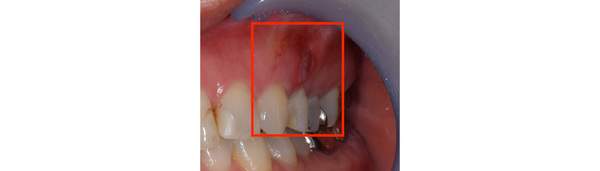

感染根管治療では根の中だけを治療しても治らないこともあります。根の先に感染物質が出てしまっているケースです。まずは根の中をきれいにし、防腐剤をつめ、その後歯ぐきをひらいて、根の先からでた感染物質を取り除きます。

その他にも、感染根管治療をしたけれども、膿がなくならない場合は、感染物質が溜まっているであろう、歯の根の先端を切り取ることもあります。

根の先に膿が溜まっています。

根の中の清掃を行い、防腐剤を詰めました。

膿の塊がなくならないため、根の先を切り取りました。と同時に膿の塊も取り除きました。

1ヶ月後。根の先の膿がなくなったことと、根の先端を切り、感染物質がなくなったことで、骨の再生が始まっています。